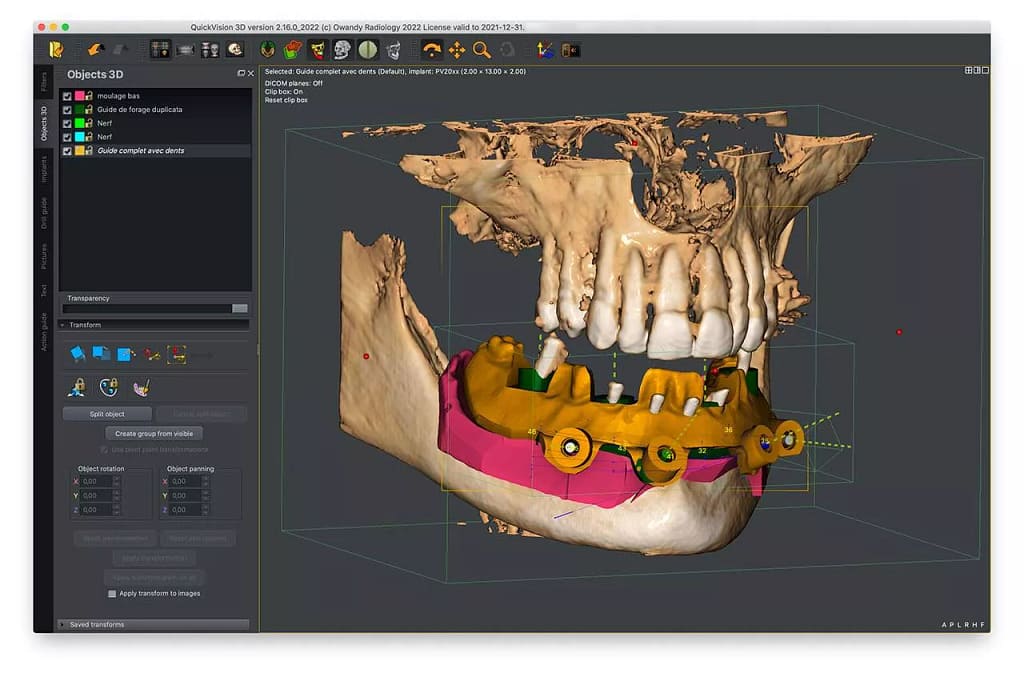

La única forma de garantizar el respeto absoluto por estas Zonas de Seguridad es mediante la Planificación Quirúrgica Digital. En nuestra clínica, la CBCT y el software de planificación 3D nos permiten:

- Mapear con precisión la ubicación tridimensional de nervios y senos.

- Determinar la longitud y el diámetro exactos del implante antes de la cirugía.

- Utilizar, cuando es necesario, Guías Quirúrgicas (cirugía guiada), que son plantillas impresas en 3D que eliminan el error humano y nos permiten replicar la planificación al milímetro en boca.